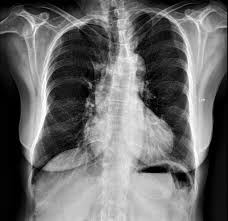

Pectus Excavatum Surgery Sternochondroplasty Versus Nuss Procedure The Annals Of Thoracic Surgery

Consult a doctor for medical advice. Maybe you would like to learn more about one of these? Pectus carinatum is an uncommon birth defect in which a child's breastbone protrudes outward abnormally. The brace is worn up to 23 hours a day and symptoms usually. Some people will also have shortness of breath,. Sometimes the deformity isn't noticeable until after the adolescent growth spurt. Check spelling or type a new query. Pectus carinatum can be treated with either a brace or surgery. The main symptom of pectus carinatum is a breastbone that sticks out. If the child's bones are still growing, a brace can help flatten the chest. We did not find results for: Sometimes the deformity isn't noticeable until after the adolescent growth spurt.